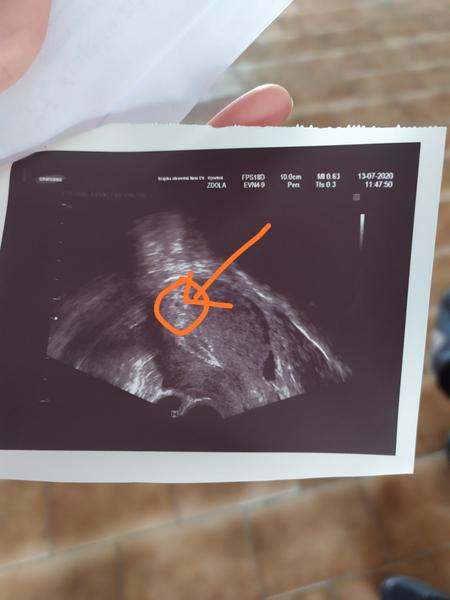

@veronikav31 krvácení nemám, bolesti občas jako na MS a občas mě bolí jakoby vaječníky,ale střídá se to, někdy v Levo někdy v pravo, dnes teda víc v právo...prodávám foto, co se na utz viděl..hodně malinkyho něco...

@kate013 ale tohle je ultrazvuk dělohy...tohle není mimoděložní těhotenství,to nejde na ultrazvuku vidět, hcg by rostlo moc pomalu a nic by vidět nebylo

@veronikav31 jako jestli jsem to dobře pochopila,tohle na fotce by teoreticky mohlo to těhotenství být....já nevím, jsem z toho zmatená :(

@kate013 ano,přesně tak, ta milinká tečka by měla znamenat těhotenství. toto je opravdu ultrazvuk dělohy, ne vejcovodu.A osobně já bych na vyčistění nešla, ne teď, určitě by bylo dobré nabrat znovu krev na hcg. já nechápu,proč doktoři posílají na vyčistění tak brzo. těhotenství může být mladší..

@veronikav31 teď jsem byla na příjmu u doktora, říkal,že 5mm něco tam je,že to těhotenství může být, ale že i nějaká tekutina v břiše,že to může být od cysty, já totiž bolesti nemám..takže zítra nic a ve středu ráno na lačno, odběr na hCG a kontrolní utz.kdyz to poroste a bude něco vidět, půjdu domů, když ne,tak na tu laparoskopii...za dva dny už by dutinka měla být větší,že?